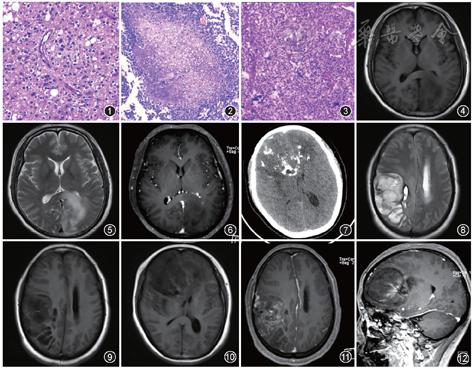

OD瘤细胞密度中等,细胞核圆居中,大小一致,比正常少突胶质细胞稍大,胞质透亮,呈典型的煎蛋样或蜂窝状特征,核周有空晕,核分裂象少或无。血管结构显示典型的分支状毛细血管网(图1)。细胞增值指数小于5%;AO瘤细胞密度高,异型性明显,核分裂象多,微血管增生,伴或不伴假栅栏样结构的坏死(图2)。肿瘤细胞核圆深染,核周有空晕,局灶性微钙化常见,血管结构以微血管增生为主(图3),也可见分支状毛细血管[2]。

好发于皮层或皮层下白质区,幕上额叶最常见,其次是颞叶,也可发生于顶叶或枕叶,团块状肿物。CT表现为混杂密度(等/低密度),常有结节状、团块状或脑回样钙化,瘤内囊变多见,出血和瘤周水肿少见,可见肿瘤邻近颅骨扩大、侵蚀。MRI表现病灶边界清楚,信号不均匀,T1WI常呈低、等信号(图4),T2WI呈不均匀高信号(图5),信号不均匀是由于钙化、囊变所致[7]。液体衰减反转恢复(FLAIR)序列呈不均匀高信号,扩散加权成像(DWI)扩散不受限或轻度受限。T2*梯度回波(GRE)或磁敏感加权成像(SWI)可显示瘤内钙化,但MRI对钙化的显示不及CT。强化方式呈无强化(图6)或轻度强化,罕见柔脑膜强化。重点强调的是,若在OD未强化区出现新的强化提示存在恶性进展。MR波谱(MRS)表现为胆碱化合物(Cho)峰增高、N-乙酰天冬氨酸(NAA)峰减低,OD缺乏脂质(Lip)峰/乳酸(Lac)峰,有助于与AO鉴别,2-羟基戊二酸(2-Hydroxyglutarate,2HG)MRS有助于识别IDH突变状态[8]。磁共振灌注加权成像(perfusion-weighted imaging, PWI)提示相对脑血容量(rCBV)增高。

好发位置及肿瘤CT表现与OD相似。常有结节状、团块状或脑回样钙化(图7),瘤内囊变多见,出血、水肿、坏死较Ⅱ级多见(图8),邻近颅骨可扩大、重塑、侵蚀。MRI表现为病灶边界不清楚,信号不均匀,T1WI呈不均匀低信号(图9,10),T2WI呈不均匀高信号,FLAIR序列呈不均匀高信号,DWI扩散不受限或轻度受限。增强扫描强化方式多变,AO较低级别OD强化更多见(图11,12),环状强化少见,若出现常提示预后不良。由于肿瘤呈弥漫浸润(图13),可在异常信号区外发现肿瘤细胞[2]。MRS表现为Cho/Cr升高,NAA峰减低,1.33 ppm可见脂质峰(Lip)/乳酸峰(Lac)(图14)。PWI表现为rCBV明显增高,能帮助鉴别Ⅱ级与Ⅲ级少突胶质细胞瘤和引导活检[9, 10]。